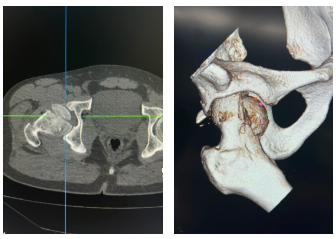

术后一个月CT

术后两月,影像检查。

术后影像学随访显示骨折愈合良好,无坏死征象,这充分证明了缝匠肌内侧入路数字化设计结合可吸收棒固定术的卓越疗效。